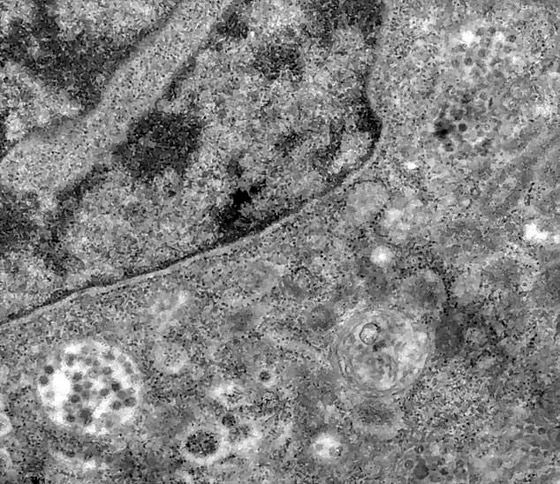

تمكّن فريق من الباحثين البرازيليين من التقاط لحظة إصابة فيروس كورونا لخلية حية، باستخدام مجهر إلكتروني قوي. والتقط خبراء من مؤسسة Oswaldo Cruz في البرازيل الصور المذهلة، أثناء دراسة طرق تكرار فيروس كورونا وانتشاره. وفي سلسلة من الصور، يمكن رؤية جزيئات متعددة من الفيروس القاتل، تنتقل من حالة محاولة دخول خلية إلى رؤيتها داخل الخلية.

واستخدم الباحثون أداة تسمح لهم بتكبير الأجسام حتى مليوني مرة من حجمها الطبيعي، ما يسمح لهم بالتعمق داخل الخلية ورؤية الفيروس. وقالت مؤسسة الأبحاث البرازيلية، Fiocruz، إن الخلايا المستخدمة في الدراسة جاءت من القرد الأخضر الإفريقي- وليس من البشر.

وغالبا ما تستخدم مزارع الخلايا من القرد الأخضر الإفريقي، وهو أحد أنواع الرئيسيات الموجودة في السودان وإثيوبيا، في الاختبارات المعملية، وفقا لـFiocruz. وتظهر أهم صورة من الصور الثلاث، لحظة بدء COVID-19 في دخول الخلية نفسها. وفي إحدى الصور، يمكن رؤية العديد من جزيئات الفيروس التي تحاول إصابة السيتوبلازم بالخلية - حيث تحافظ على المادة الجينية.

وكتب فريق البحث أن "العلماء استخدموا الفيروسات المعزولة من عينات تم جمعها من أنف وحلق مريض مصاب. ثم تُنقل الخلايا المصابة إلى المختبر حيث يتم فحصها تحت المجهر الإلكتروني، لالتقاط لحظة الإصابة". وتظهر البقع الداكنة في الصور التي التقطها الباحثون، فيروس SARS-COV-2.